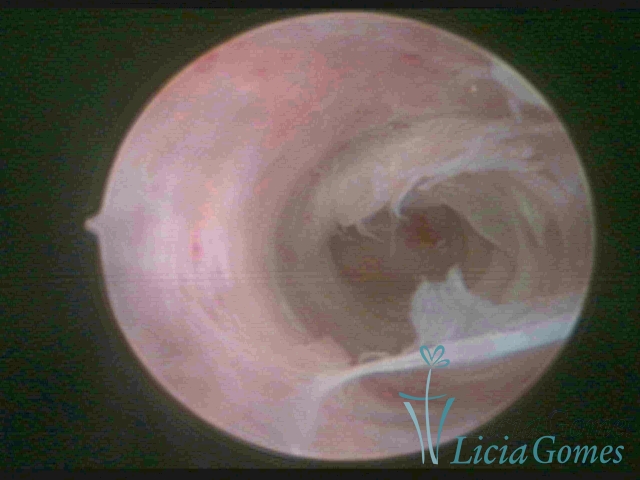

• SINÉQUIA TIPO FIBROMUSCULAR